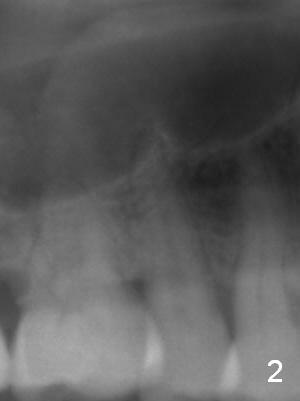

A 61-year-old man (WJ) cracked the tooth #31 after RCT. Four years after #31 extraction, the tooth #4 cracks by itself. The apex of the tooth appears to protrude into the sinus and is closely associated with the sinus septum (triangle: Fig.2,3). An implant will reach the top of the socket for stability (Fig.4 black area). The abutment is expected to be 4.8x4(3) (SM) or 4.5x4(3) (UF) mm. Metronidazole will be used for disinfection of the socket. On returning, he requests #31 implant.